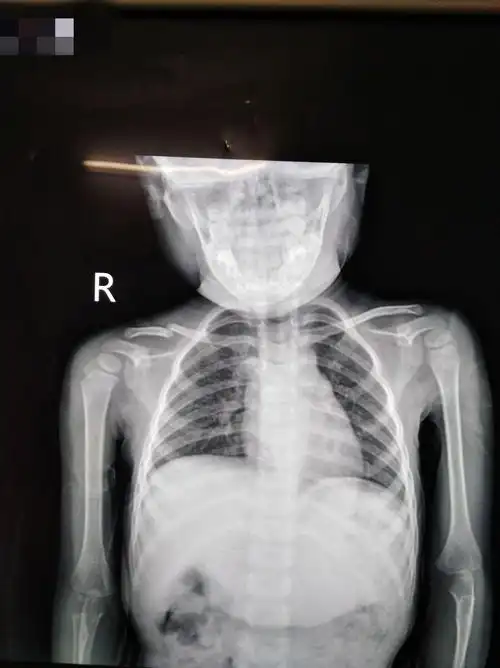

一岁半小儿锁骨骨折治疗一例.

小儿锁骨骨折克氏针内固定

少儿锁骨骨折内固定手术一例